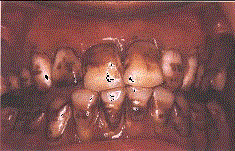

问题 关于氟斑牙,下列哪个说法是错误 ( )

选项 A.氟主要损害釉质发育期牙胚的造釉细胞 B.饮用水是摄人氟的最大来源 C.深层釉质含氟量是表面釉质的11倍左右 D.又称斑釉牙 E.慢性氟中毒患者可有骨骼增殖性变化

答案 C